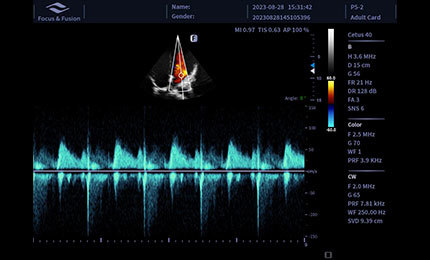

cw

Tryb CW wykorzystywany jest do analizy przepływów o wysokich prędkościach, szczególnie w diagnostyce kardiologicznej. Umożliwia dokładną ocenę zwężeń oraz niedomykalności, zapewniając wiarygodną analizę parametrów hemodynamicznych.